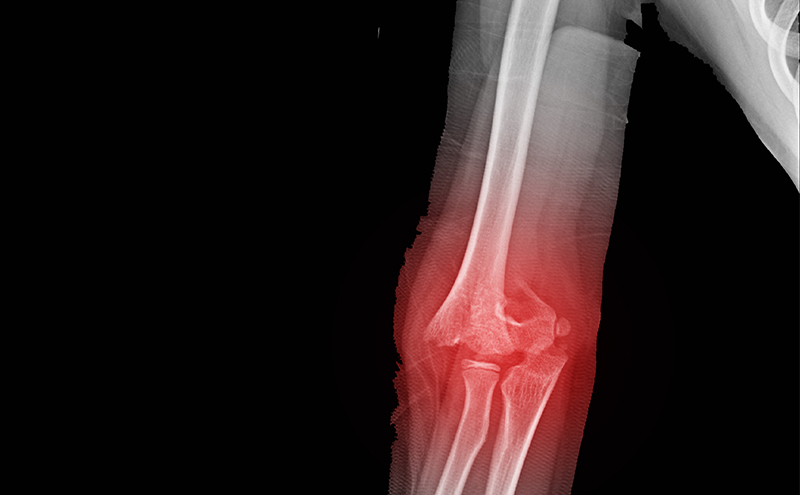

Supracondylar Fracture

A 4- year-old girl comes in with her parents for evaluation of acute left arm pain after a fall from monkey bars. She has her left arm held in a fixed and adducted position. On physical exam there is isolated tenderness of the left elbow, without any swelling, bruising, or open wounds. The patient is able to actively pronate with only mild discomfort. She is otherwise neurovascularly intact, and the rest of the examination is unremarkable. You notice an ultrasound machine by the bedside. What are the findings and scanning technique used when evaluating the elbow joint with point-of-care ultrasound?

Supracondylar fractures in pediatrics are a common diagnosis in the emergency department. Garland Type II to IV fractures are displaced and fairly obvious on radiographs. These will require close reduction, orthopedic surgical consultation, and likely surgical pinning. Garland Type I are non-displaced supracondylar fractures. They are often subtle and may be missed on plain radiographs as a fracture line may not be detected. Rather, occult elbow fractures are often diagnosed by the presence of an enlarged triangularly shaped anterior fat pad known as the “sail sign” and/or the presence of a posterior fat pad. One should also be sure to look at the anterior humeral line on the lateral view to ensure it intersects the middle third of the capitulum in children greater than five years of age; if it does not, it may also indicate a supracondylar fracture. However, plain radiographs may still miss these findings, and ultrasound can supplement your workup and assessment – pointing you to the appropriate treatment plan.